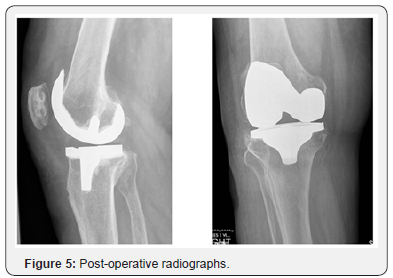

A 74yr male with a past medical history of osteoarthritis bilateral shoulders, coronary artery disease, congestive heart failure with cardiomyopathy, hypertension, peptic ulcer disease, gastric reflux, type 2 diabetes mellitus, gout and varicose veins presented with chronic right knee pain with associated subcutaneous bursa on his right leg that had been progressively increasing in size for 8-9 years (Figures 1-4). As the bursa could be decompressed entirely from an anterior midline incision, it was decided by the surgeon that the bursa would be removed at the same time as the total knee arthroplasty. The patient underwent excision of a massive subcutaneous bursa found over the anterolateral and posterolateral aspect of the leg (Figures 5-8) utilizing a midline incision, following which a total knee arthroplasty was performed using a medial parapatellar arthrotomy. The tourniquet was inflated during the procedure and was released before closure with a tourniquet time of 110 minutes. The wound was closed in layers over four 1/8th inch hemovac drains (2 placed in the joint and 2 placed in the bursal cavity).